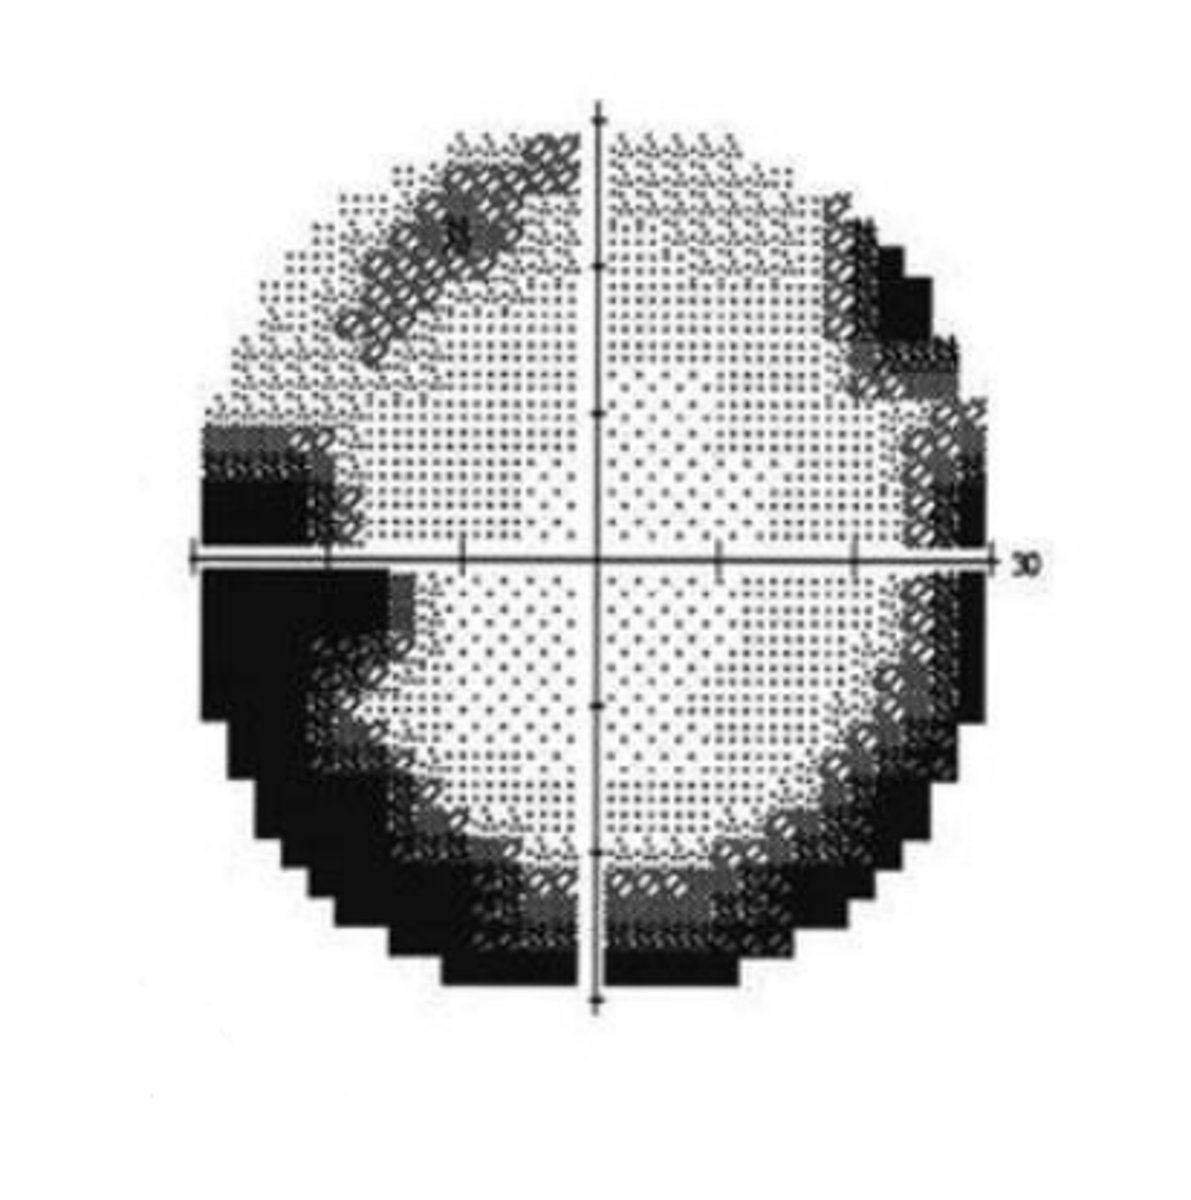

Grayscale

presentation of VF results that gives a visual representation of sensitivity. Is useful for detecting artifacts and overall regions of concerns, but should not be used to assess the actual defect in detail.

clover

If a patient is fatigued, this will commonly produce a visual field defect in the shape of a _____. This is because the center of the quadrants are tested first.